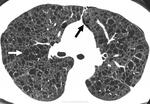

лимфангиолейомиоматоз

Типичный пример патологии при которой основным патерном являются кисты - :

Продолжение.

Лимфангиомиоматоз.

Лимфангиолейомиоматоз.